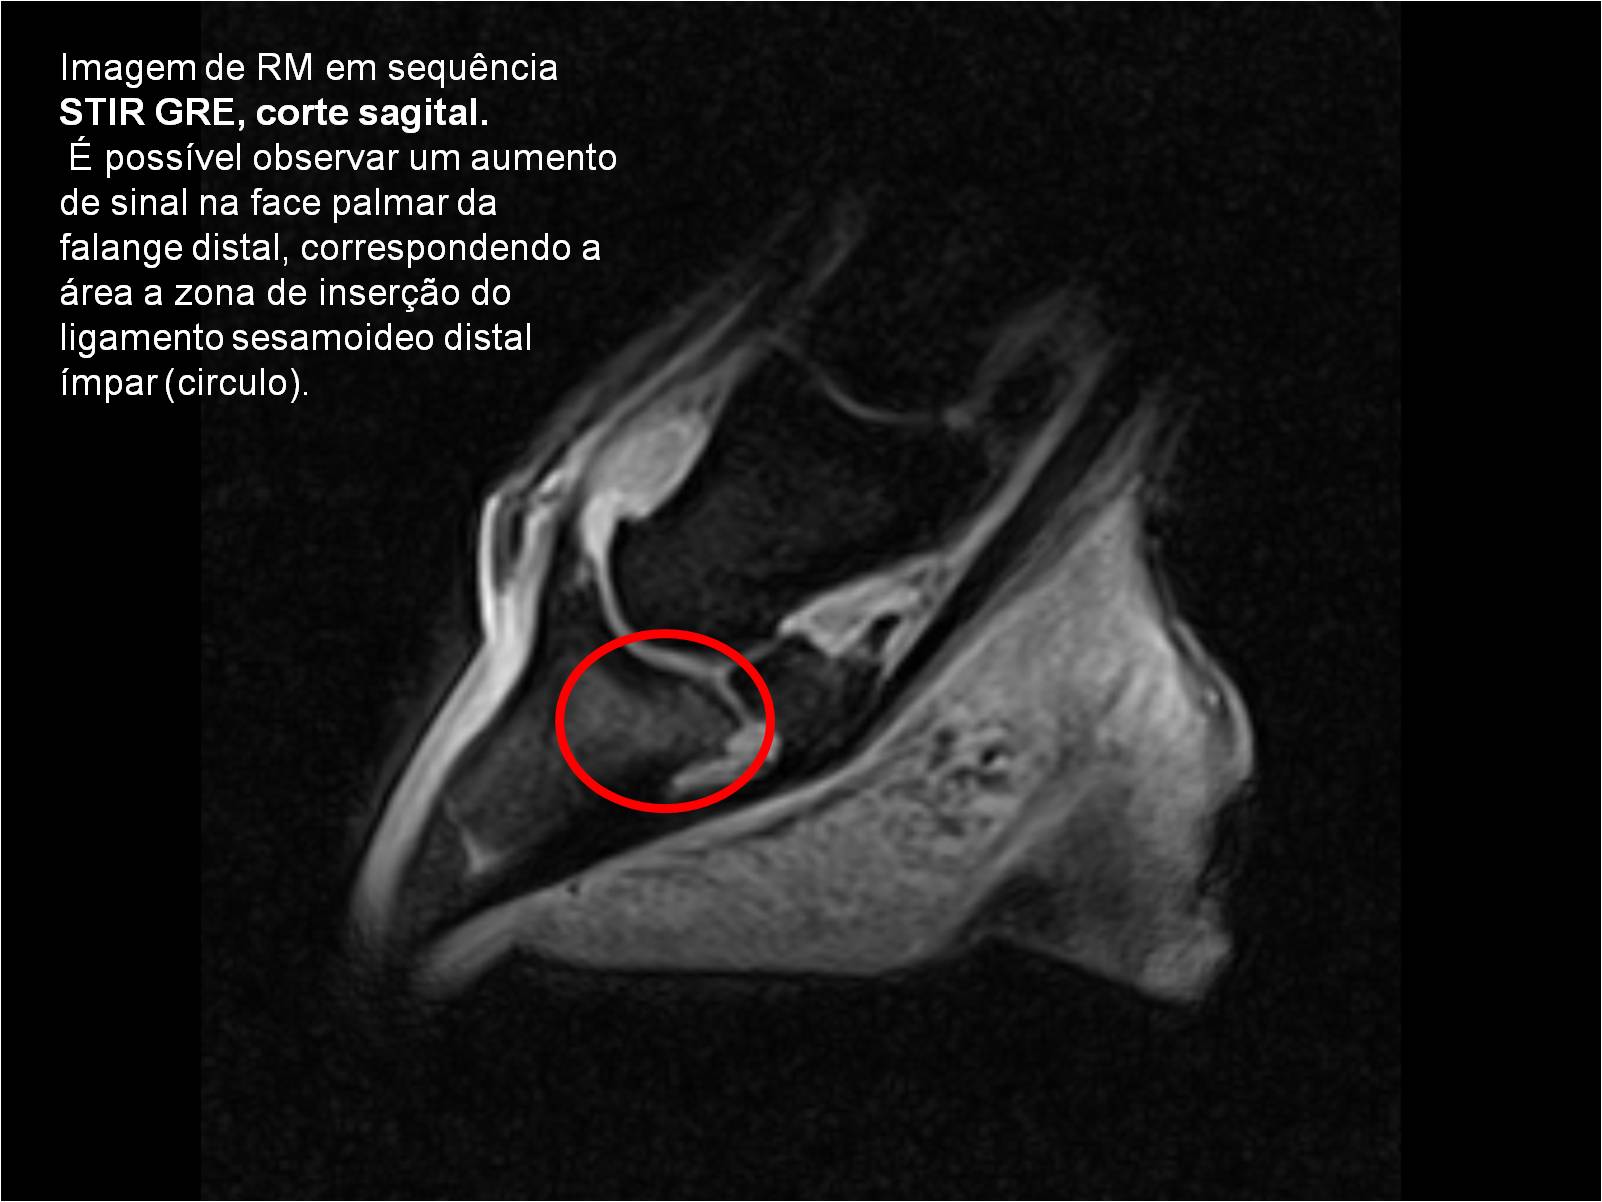

Publisher: Universidade de Évora

Abstract: O relatório de estágio encontra-se estruturado em três partes distintas. A primeira parte faz a caracterização das infraestruturas e funcionamento do Hospital Veterinário de Equinos de Lüsche, Oldenburg, Alemanha, assim como a análise casuística dos casos clínicos acompanhados durante os 6 meses de estágio. A segunda parte consiste de uma revisão bibliográfica sobre quistos do osso subcondral em equinos. Por fim, a terceira parte consta da apresentação e discussão de um caso clínico, nomeadamente o diagnóstico e acompanhamento imagiológico, por ressonância magnética, de um quisto subcondral na terceira falange num cavalo adulto; ### Abstract Equine Practice- Subcondral bone cyst of the third phalanx This internship report is divided in three parts. The first part characterizes the infrastructure and function of the Equine Hospital Lüsche, Oldenburg, Germany, as well as the casuistic of the clinical cases accompanied during the 6 month internship. The second part consists in a bibliographic review of cystic lesions of the subchondral bone in equines. The third part consists in a case report, the diagnostic and imagiological accompaniment, by use of magnetic resonance imaging, of a subchondral bone cyst in the distal phalanx of an adult equine.